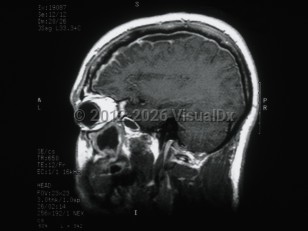

Herpes simplex virus encephalitisHerpes simplex virus encephalitis

Subdural empyemaSubdural empyema

Meningoencephalitis